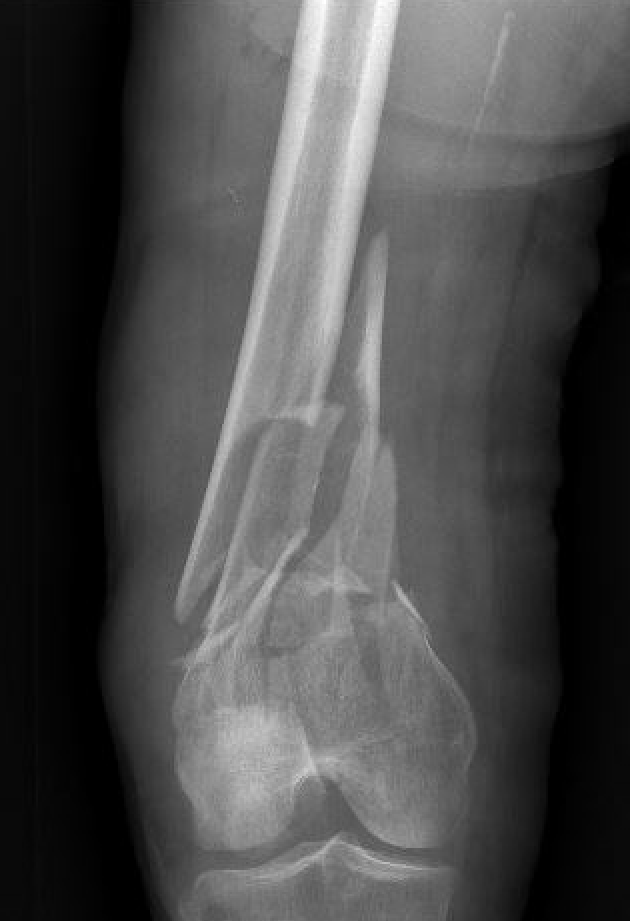

Xray

Options

Lateral plate

Retrograde IM nail